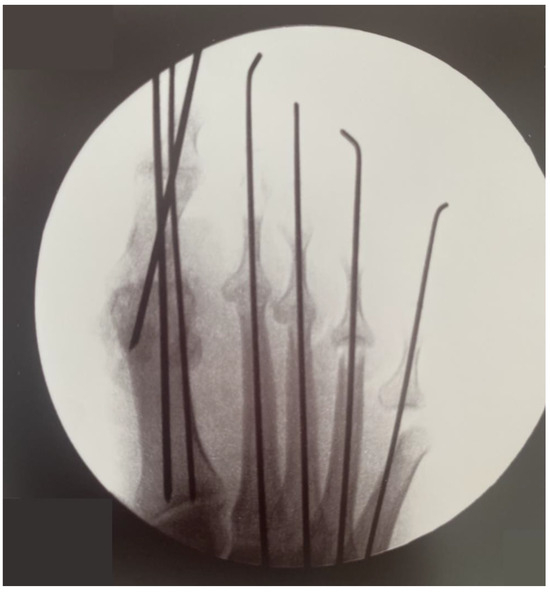

Osteosynthesis was performed using K-wires (Figure 3). Three 2 mm K-wires were used for the triplanar fixation of the hallux arthrodesis, and 1.6 mm K-wires were used for the fixation of the IFP joints.

In addition to metatarsophalangeal (MTP) joint fusion, medial and lateral soft tissue balance was carefully evaluated during the second surgery. Intraoperative dynamic testing was conducted using temporary fixation with K-wires to verify passive hallux alignment and identify abnormal stress patterns. This approach enabled the selective release of the medial capsule to alleviate excessive tension while preserving the integrity of the lateral sesamoid ligaments. These measures ensured an even distribution of forces and optimized functional outcomes following the fusion procedure.

Figure 3. Postoperative AP radiograph of the right foot showing correction of hallux varus and lesser toe deformities with K-wires.